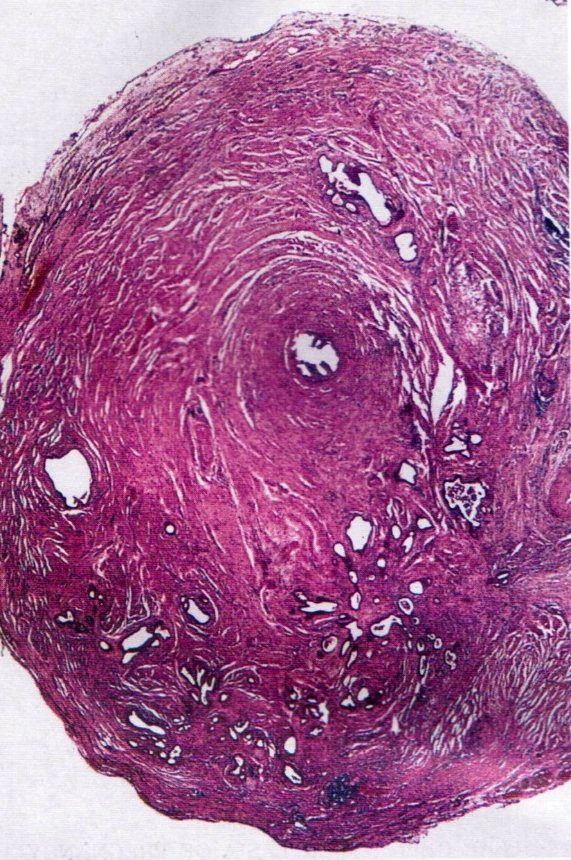

Gross description

- Firm, nodular swellings of the fallopian tube, ranging in size up to 2 cm in greatest dimension (Br J Radiol 2021;94:20201386)

- May be unilateral or bilateral

- Smooth, intact serosal covering

- Cross section of the nodules reveal gray, yellow or brown tissue punctuated by small cysts that surround the original tubal lumen (StatPearls: Salpingitis Isthmica Nodosa [Accessed 22 June 2023])

- Nodosity of the isthmus may give the uterus a horned appearance

Gross images